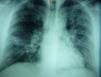

Un hombre de 39 años (gran fumador, hipertenso y moderadamente obeso) acudió a la Unidad Interna de Atención en octubre de 2012 por un cuadro de disnea de 3 días de evolución con tos productiva paroxística y dolor retroesternal, sin fiebre. Se detectaron crepitaciones leves al final de la espiración en los campos pulmonares medios y bajos de forma bilateral, asociadas a una fase espiratoria medianamente prolongada y leucocitosis leve. El paciente rechazó el ingreso hospitalario y 2 días más tarde regresó por agravamiento de una intensa disnea en reposo, con frecuencia cardiaca de 130 latidos por minuto y fiebre (38,5°C). Una nueva radiografía de tórax reveló infiltrados alveolares más intensos, difusos y extendidos por todo el pulmón izquierdo y el campo medio del pulmón derecho (fig. 1). En el análisis rutinario de sangre se halló leucocitosis, aumento de neutrófilos y monocitos, aumento relativo de PCR (7,5mg/dl), VSG (73mm/h), ALT (83U/L) y LDH (484U/L).